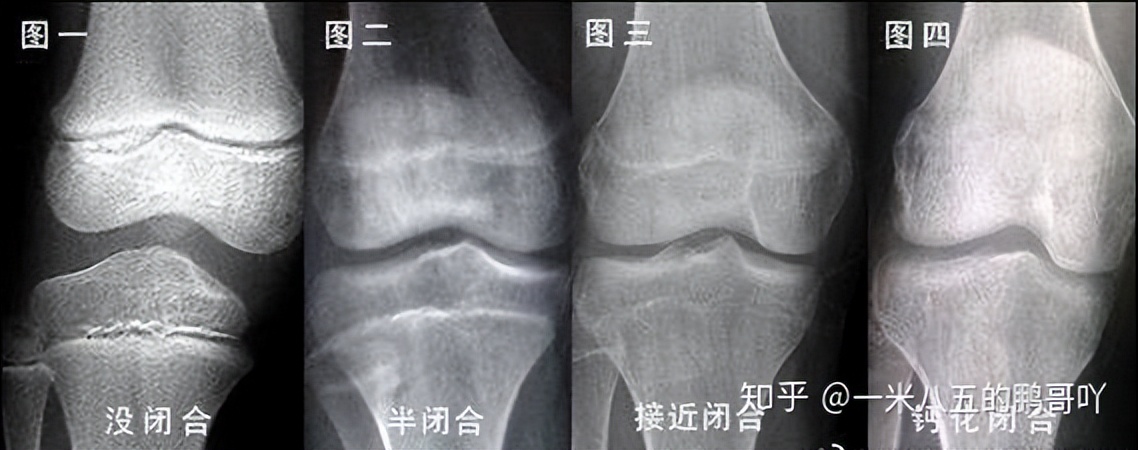

*局骗**二:筋膜枪可以辅助增高

生物学表明人的身高由先天源传基因和后天营养摄入决定,遗传因素占70%,营养因素占30%,特别是青少年骨垢线闭合后几乎不可能再通过任何外界施力增高。筋膜枪的主要功能是按摩肌肉组织,并不能对增高起到任何作用,错误过度的击打还会造成肌肉损伤。